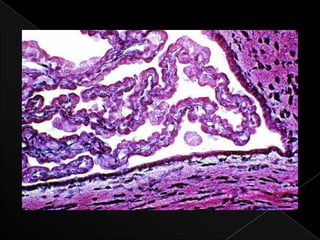

CORTEZA › COMPUESTA POR:  CAPA MOLECULAR:  CAPA MAS EXTERNA  LOS CUERPOS NEURONALES (PERICARION) SON PEQUEÑOS Y RELATIVAMENTE ESCASOS  CAPA DE CELULAS DE PURKINJE:  SON FACILMENTE DISTIGIBLES POR SU LOCALIZACION, GRAN TAMAÑO, Y EXTENSIVA ARBORIZACION DENDRITICA  CAPA GRANULAR:  CELULAS CON CITOPLASMA GRANULAR. AREA DE SINAPSIS ABUNDANTES.

• 26.

MEDULA: › CORRESPONDE ALA SUSTANCIA BLANCA DE LOCALIZACION INTERNA UBICADA POR DEBAJO DE LA CAPA GRANULAR. › COMPUESTA PRINCIPALMENTE DE FIBRAS MIELINIZADAS Y CELULAS DE LA NEUROGLIA ASOCIADAS.